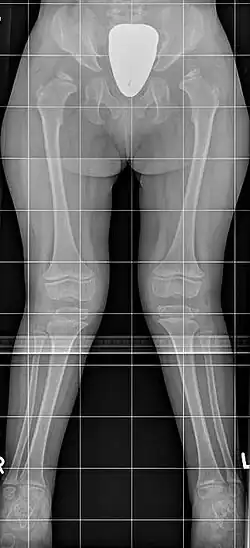

![]() Синдром Моркио: на рентгенограмме с двух сторон отмечается укорочение шейки бедра, в результате чего уменьшается поперечник таза; крылья подвздошных костей неправильной формы; характерна вальгусная деформация нижних конечностей | |